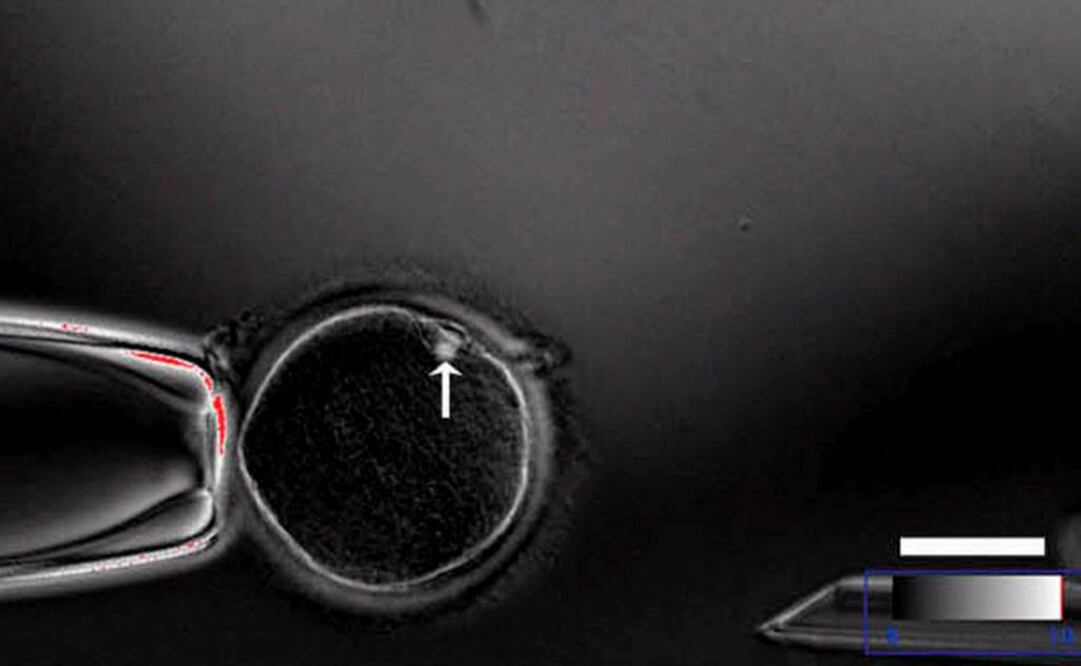

Utilizando 26 embriones "con taras y no aptos para tratamientos de fertilidad", en palabras del líder del equipo médico, Fan Yong, se logró que cuatro de ellos desarrollaran inmunidad frente al VIH, aunque el resto mostraron mutaciones "no planeadas".

La investigación fue publicada en el último número del Journal on Assisted Reproduction and Genetics, donde se aclara que todos los embriones fueron destruidos a los tres días.

La modificación se realizó mediante una nueva técnica llamada CRISPR-Cas9 que según señaló a la revista especializada Nature el biólogo estadounidense George Dailey, experto en células madre, ha sido el principal éxito del equipo médico cantonés, al lograr éste una modificación genética más precisa de lo habitual.